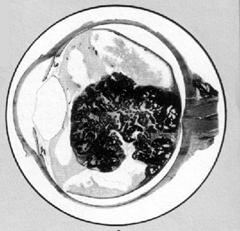

Examenul fundului de ochi, atunci este posibil pune diagnosticul; tumora se poate dezvolta fie in zona centrala, fie mai rar in zona retiniana periferica. Aspectul tumorii este de masa alba nodulara, proeminenta in corpul vitros, cu prezenta de hemoragii si vase de neoformatie pe suprafata. In alte situatii aspectul oftalmoscopic este de decolare de retina de culoare cenusie, fara ruptura (Fig. 17.10/11).

Fig. 17.11 -

Retinoblastom sectiune prin glob Fig. 17.10 -

Retinoblastom aspect oftalmoscopic